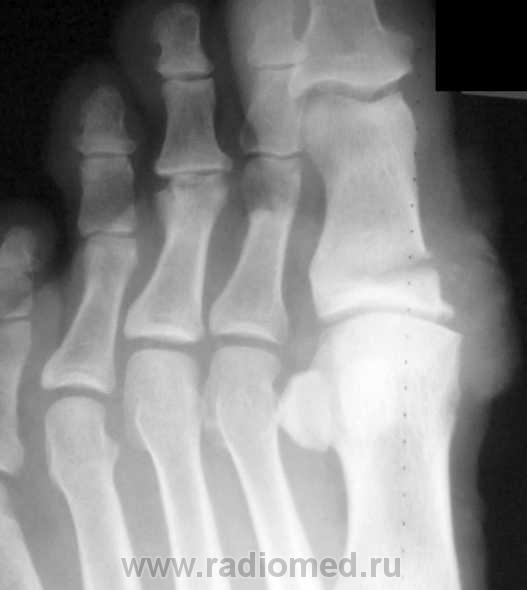

Очередной случай

Изображение

По большому счету, это уже набор изображений, характеризующих определенный профессиональный травматизм, а данная тема становится актуальной, не только в плане диагностики, но и в векторе вопросов техники безопасности, возможно даже на производстве.